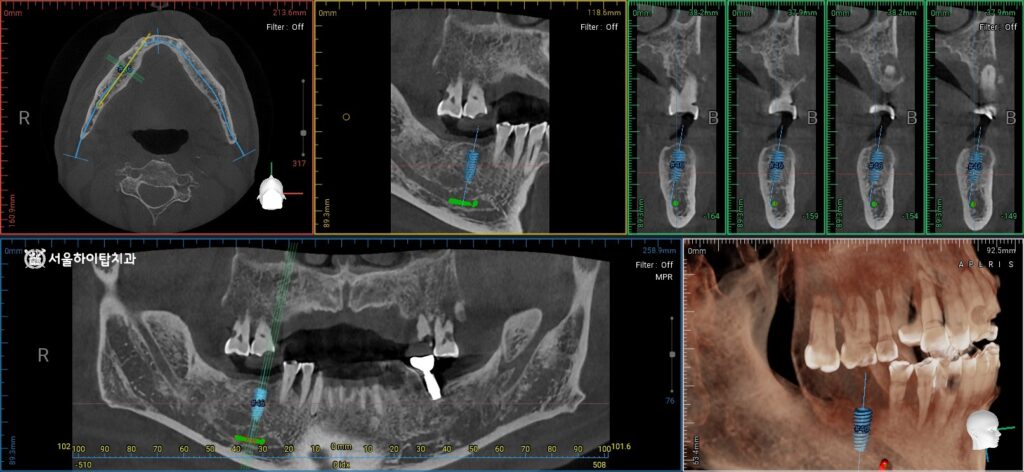

CT 기반 임플란트 수술 가상 시뮬레이션

동암역 치과 에서는 임플란트 식립 전, 가상 시뮬레이션을 통해

임플란트가 심겨질 위치와 각도, 깊이를 정확히 계획할 수 있다고 설명해 드립니다.

이를 통해 구치부 골의 폭과 높이,

주변 해부학적 구조물과의 안전 거리 등을 사전에 확인할 수 있어,

수술 중 발생할 수 있는 위험을 최소화하고,

임플란트의 장기적 안정성과 저작 기능 회복을 동시에 확보할 수 있습니다.

현재 해부학적 구조물인 하치조 신경과의 거리도 충분하며,

남은 골량 또한 임플란트 식립을 진행하기에 적절한 상태로 확인됩니다.

이를 바탕으로, 구치부 임플란트는 안전하게 식립할 수 있으며,

향후 저작 기능 회복과 교합 안정화에 유리한 조건을 갖추고 있습니다.